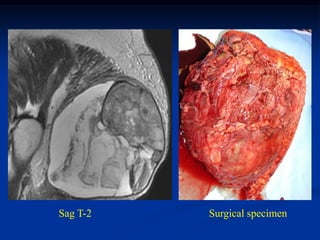

Case #1204.1

31 year female with soft swelling in leg for many years

Axial CT

Cor Ct

Cor T-2   Sag Gad   Sag Gad

Axial Gad   Axial Gad